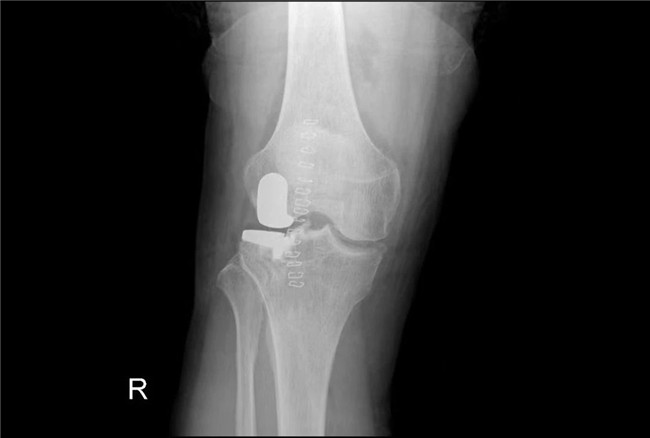

一個(gè)單髁置換手術(shù)要想達(dá)到理想的手術(shù)治療效果并不簡(jiǎn)單,這與假體的大小、方向和松緊度密切相關(guān),其中任何一點(diǎn)出現(xiàn)差池,結(jié)果都會(huì)差強(qiáng)人意。為此,羅主任團(tuán)隊(duì)在術(shù)前和術(shù)中進(jìn)行了精確的設(shè)計(jì)和測(cè)量,制定周密手術(shù)方案,順利為病人實(shí)施手術(shù),幫助膝關(guān)節(jié)“補(bǔ)牙”。

▲術(shù)后假體位置良好,外側(cè)間隙恢復(fù)▲